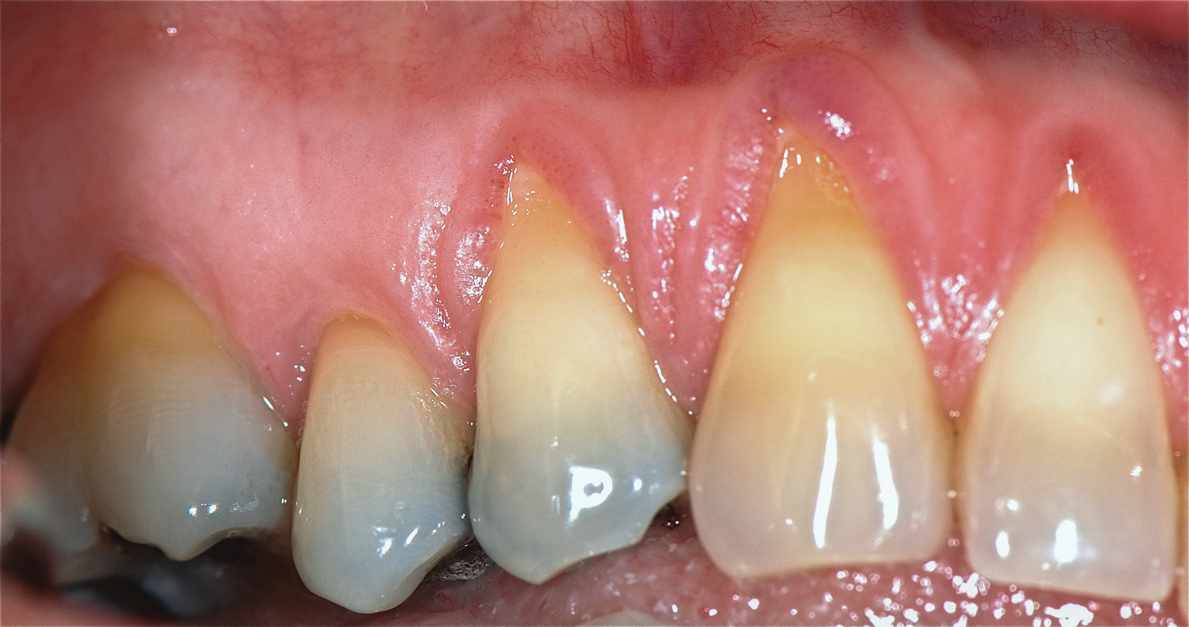

The workshop's group on periodontal soft-tissue root coverage procedures evaluated the predictability of root coverage procedures for single- and multiple-tooth Miller Class I and II10 periodontal recession defects. The workshop concluded that predictable root coverage was possible for Miller Class I and II recession involving a single tooth. When compared with the use of acellular dermal matrix graft (ADMG) (donor tissue) or EMD (porcine origin), procedures using a subepithelial connective tissue graft (SCTG) harvested from the patient's palate provided the best root coverage outcomes in conjunction with a coronally advanced flap.11 As alternatives to autogenous donor tissue, the workshop found strong evidence to support the use of an ADMG or EMD in conjunction with a coronally advanced flap and limited evidence to support the use of platelet-derived growth factor and xenogeneic collagen matrix.11 In addition, root coverage procedures were found to be effective for Miller Class I and II recession defects affecting multiple teeth, although the evidence is limited.11 Figure 1 and Figure 2 show the pretreatment and 1-year postoperative views of a soft-tissue root coverage treatment with SCTG and EMD that used a coronally advanced flap and a tunneling procedure. Figure 3 and Figure 4 depict the pretreatment and 3-year postoperative views of a root coverage procedure with ADMG and EMD that used a coronally advanced flap and a tunneling procedure (this patient was noncompliant following surgery and did not return to the office until the 3-year postoperative appointment).

(1.) Pretreatment view of single incisor with gingival recession exposing the root.

Figure 1

(3.) Pretreatment view of recession affecting multiple maxillary teeth.

Figure 3